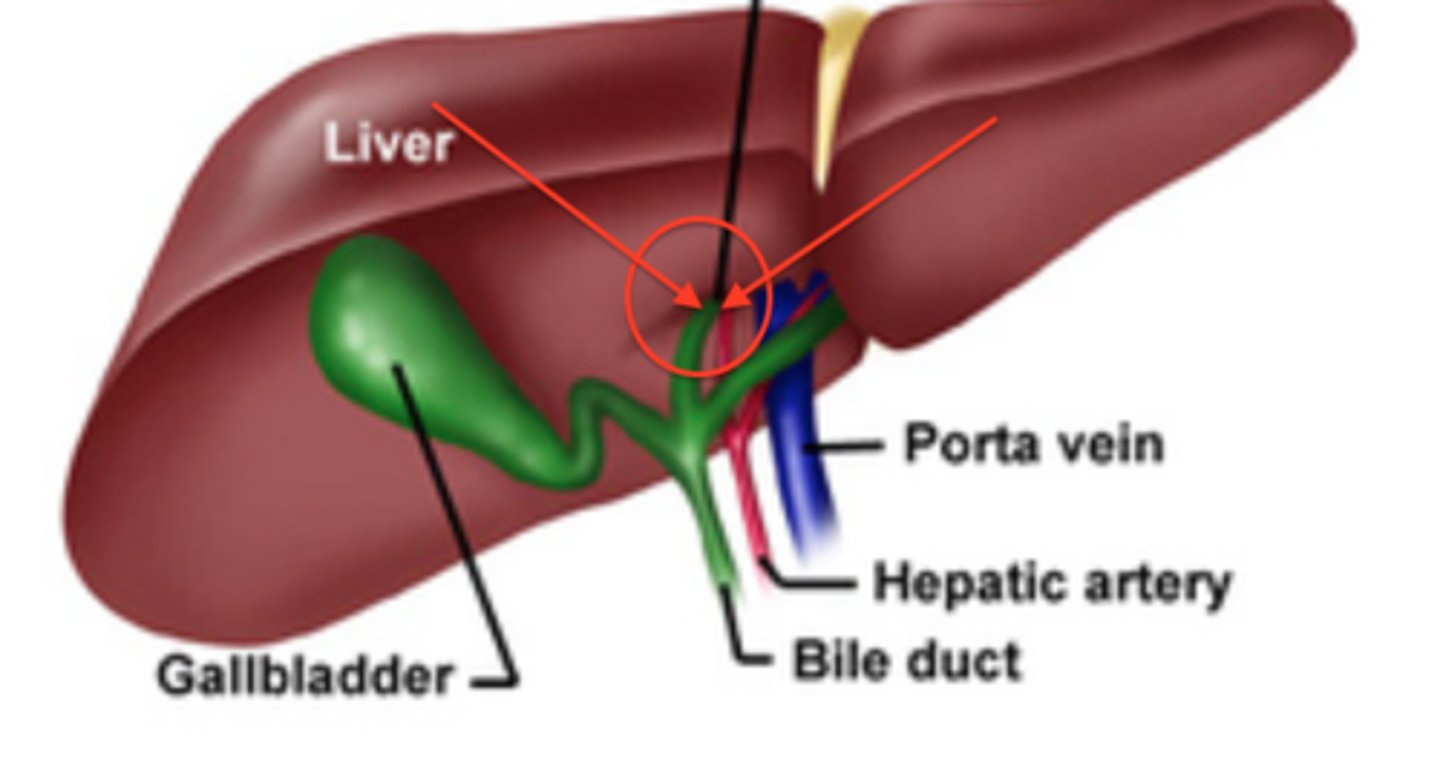

porta hepatis

where the blood and lymph vessels, bile ducts, and nerves enter and leave the liver

hepatic artery proper

common bile duct

common hepatic duct

cystic duct

hepatic portal vein

gallbladder